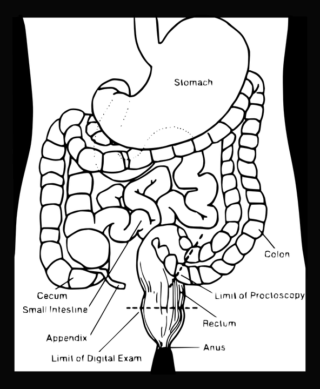

Perianální fistule (píštěle v oblasti konečníku) provázející Crohnovu nemoc jsou nepříjemnou komplikací, která se mnohdy velmi těžko léčí. Jedná se o vznik kanálků, které mohou propojovat

Nádorová onemocnění v oblasti pánve mnohdy vyžadují radiační terapii. Ta však vede k poškození sliznic, které může být spojené s chronickými záněty, jak to vidíme